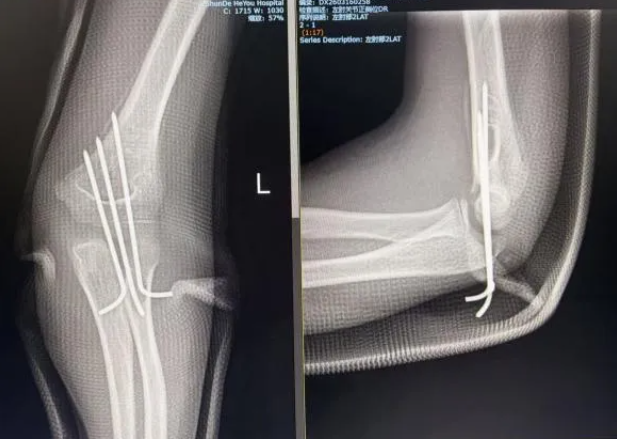

手术治疗:微创技术保障功能恢复

当骨折属于 Gartland Ⅲ型(完全移位)或合并血管神经损伤、手法复位不理想时,则需要考虑手术干预 。

目前,闭合复位经皮克氏针内固定术(CRPP)被公认为首选方案 。

核心优势:最大程度减少了对软组织和骨膜血运的破坏,不仅有利于愈合,还能避免留下明显的手术瘢痕 。